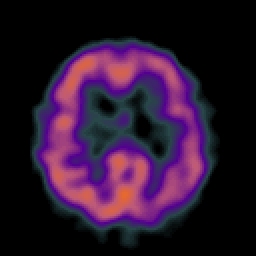

Alzheimer's Disease: SPECT/fMRI overlay -- Slice #7

[Home][Help][Clinical] Slice 7